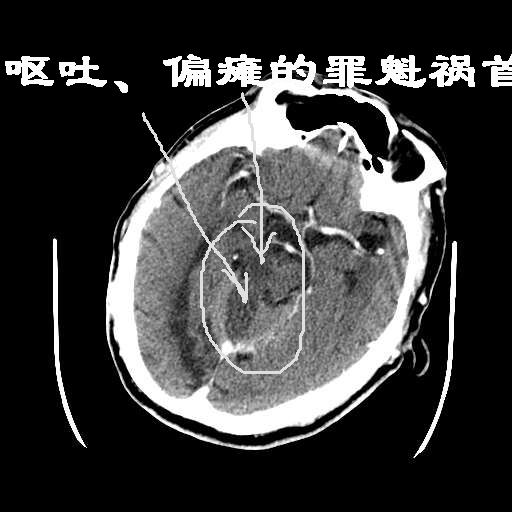

皮脑应该可以诊断,不知道增强病灶有没有强化(ct值),从片上看好像有轻度强化,定位像是脑外的,圆形高密度,内部有点状更高密度考虑为点状钙化,首先考虑为脑膜瘤.鉴别诊断:胶质瘤,垂体瘤,听神经瘤等.

这次病变主要是是因为脑干及小脑的梗塞,另外原有多发脑梗塞。右侧鞍上池及颞叶区可见一大部钙化的病灶,强化后略有增大,并见一条血管进入,考虑血管瘤。不排除脑膜瘤可能!~!

无占位,无水肿带,大部分钙化,av畸形?增强的图片都不尽量在同层面,难比较强化,如果有强化迹象肯定是av畸形!

无占位,无水肿带,大部分钙化,av畸形?或钙化灶?多发腔梗

考虑:颅底脑膜瘤。双侧基底节区脑腔隙性脑软化灶。脑萎缩。脑白质变性。

考虑血管瘤。不排除脑膜瘤及单纯钙化可能!